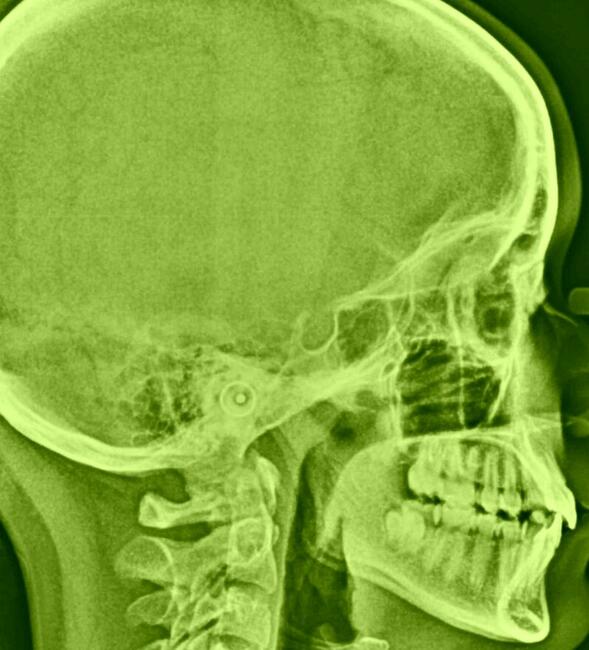

zdjęcie RTG Cefalometryczne

zdjęcie RTG Cefalometryczne, profesjonalny przegląd i pomiar zdjęć RTG cefalometrycznych do badań ortodontycznych, badanie jamy ustnej i czaszki, diagnostyka stomatologiczna, ortodoncja, analiza twarzy i czaszki, ocena wzrostu szczęki i żuchwy, wykrywanie wady zgryzu, planowanie długoterminowego leczenia ortodontycznego, precyzyjne pomiary, radiografia, zdjęcie rentgenowskie, ortodoncja.Zdjęcia wykonujemy na bieżąco w godz. 8.00-18.00, wyniki wydawane są po wykonaniu badania , zdjęcie RTG na kliszy, na CD i mejlem do lekarza.